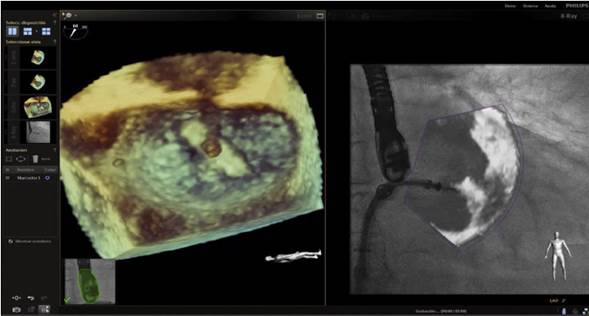

En respuesta a las necesidades de buenos resultados y seguridad para el paciente durante la realización de procedimientos complejos, se desarrolló un software capaz de fusionar la fluoroscopia y la ecocardiografía transesofágica 2D/3D13 en una sola imagen (figs. 2 y 3). Viene utilizándose cada vez con más frecuencia, con múltiples reportes en la literatura, pues ha mostrado sus buenos resultados de eficacia y especialmente de seguridad, dando la posibilidad de su implementación en la rutina diaria.

Figura 2 Imagen de fusión en ecocardiograma transesofágico 3 D cuatro cámaras; se observa guía que pasa a través de septo interauricular durante colocación de Mitraclip.

Figura 3 Imagen de fusión. Se observa paso de camisa en el septo interauricular comenzando giro hacia la válvula mitral para colocación de Mitraclip.